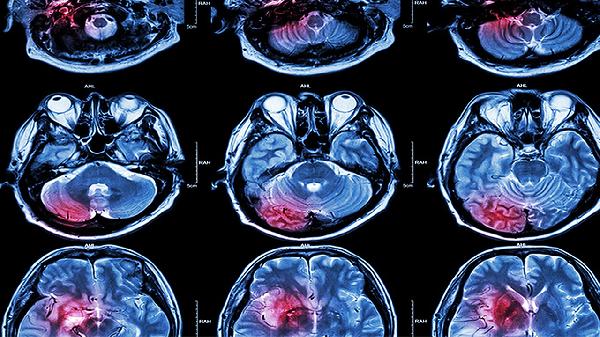

双侧脑室旁缺血灶怎么回事

双侧脑室旁缺血灶可能由高血压、脑动脉硬化、糖尿病、高脂血症、脑血管痉挛等原因引起,可通过控制基础疾病、改善生活方式、药物治疗、康复训练、定期复查等方式干预。1、高血压 长期血压控制不佳会导致脑小动脉